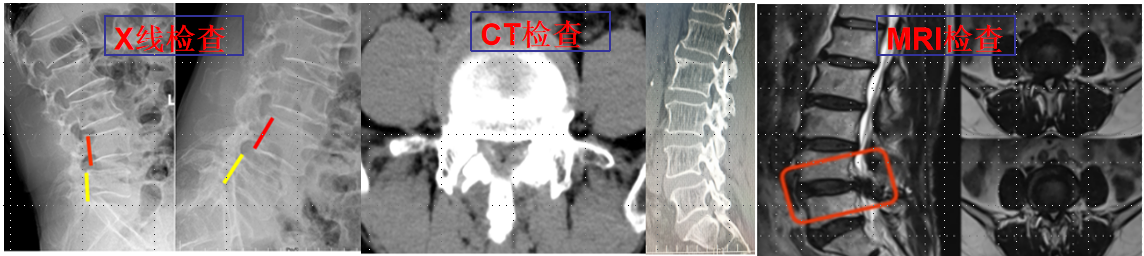

椎間孔鏡技術(shù):

利用椎間孔鏡從患者腰椎側(cè)方或者后方進(jìn)入達(dá)到椎間盤突出或者其他病變部位,用專用工具將突出(脫出)的椎間盤組織或病變?nèi)〕觯ㄈコ亩_(dá)到治療椎間盤突出或者椎管狹窄的目的。它的優(yōu)勢在于:局部麻醉、微創(chuàng)、切口小(僅約7mm)出血少,恢復(fù)快(第二天即可佩戴硬腰圍下地)及療效好。

539650c2baae42ea976bd4bf6a4f7947.Png